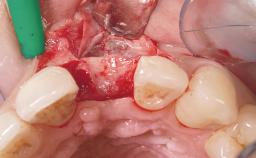

Immediate Flapless Placement of an Implant in a Maxillary Left Central Incisor Site

A 29-year-old female patient presented for treatment to replace the upper left central incisor tooth with an implant- supported restoration. The tooth had been intermittently symptomatic for the previous 12 months. The tooth had originally suffered trauma about 15 years previously. Several endodontic treatments had been performed, including an apicectomy procedure to retain the tooth. The patient was healthy and a non-smoker. She had reasonable expectations in regard to esthetic outcomes and the risk of marginal tissue recession following treatment. At medium smile, the gingival margins of the upper teeth were visible, with a display of 3 to 4 mm of the gingival margins. Gingival recession of tooth 21 and a discrepancy in the gingival levels between teeth 11 and 21 was observable during normal speech and smile.

Soft Tissue Grafting None

Soft Tissue Contour and Volume Slightly compromised